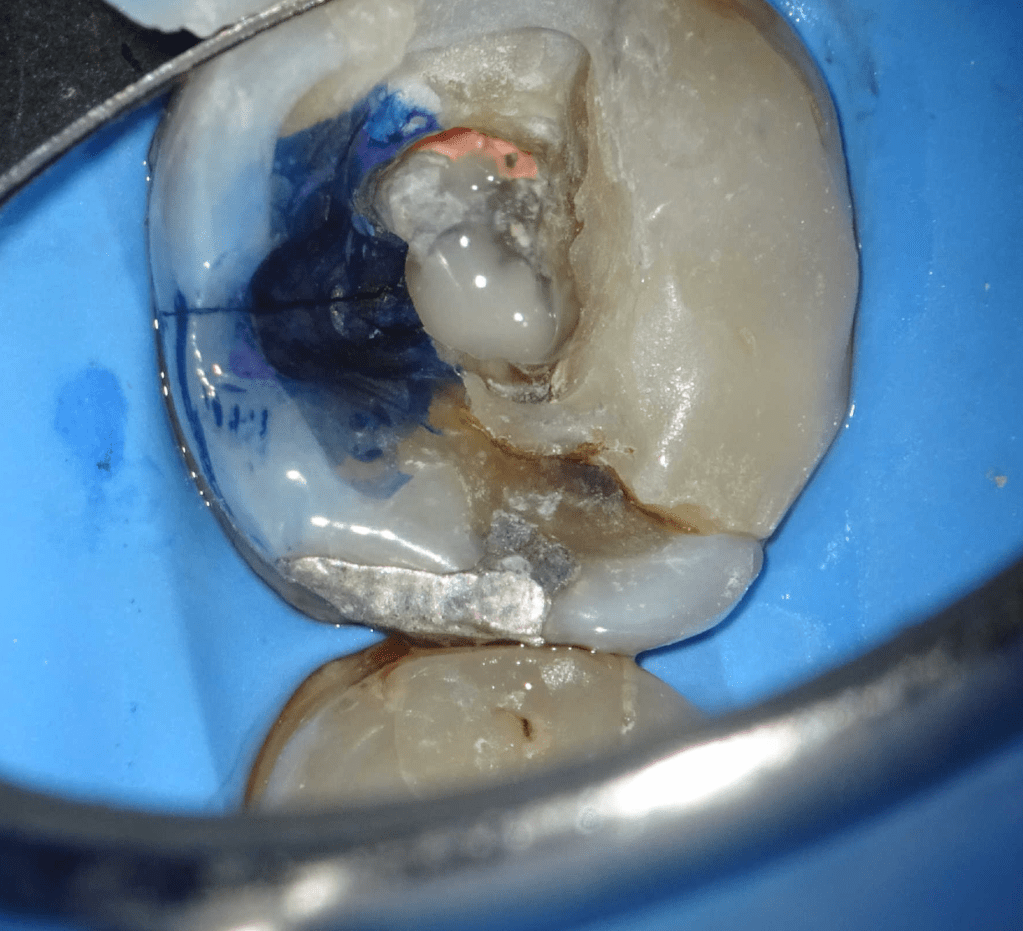

Fisura, remoción amalgama para explorar